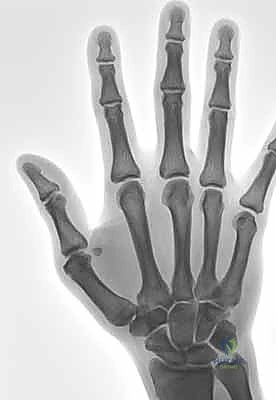

2. التصوير بالأشعة السينية (X-rays)

يُعد التصوير الشعاعي الخطوة الأولى لاستبعاد وجود كسور مصاحبة. في كثير من الأحيان، ينسلخ الرباط ويسحب معه قطعة صغيرة من العظم (Avulsion fracture). كما يتم أخذ صور أشعة تحت الإجهاد (Stress X-rays) لتوثيق عدم الاستقرار.